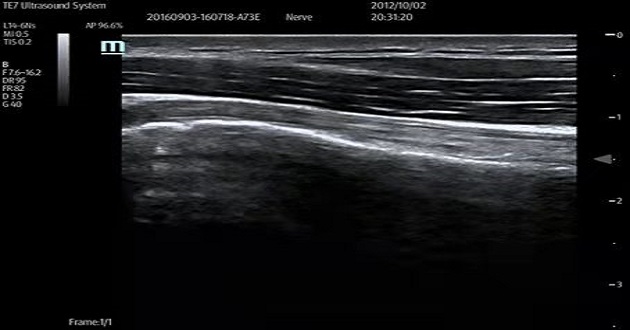

Mindray's specialized musculoskeletal (MSK) ultrasound solutions provide physicians with a set of cutting-edge, professional, and comprehensive ultrasound innovative support services. Mindray's proprietary ZST+ Platform known as the zone sonography and 20MHz UHF probe serve as the breakthrough technologies for excellent imaging. CEUS, shear wave elastography and other comprehensive high-end features can not only meet the current clinical needs, but also be able to scale up for the future needs. Various advanced puncture functions make it possible to achieve one-stop future musculoskeletal diagnosis and treatment solutions.

img-4

Musculoskeletal (MSK) Ultrasound

img-3